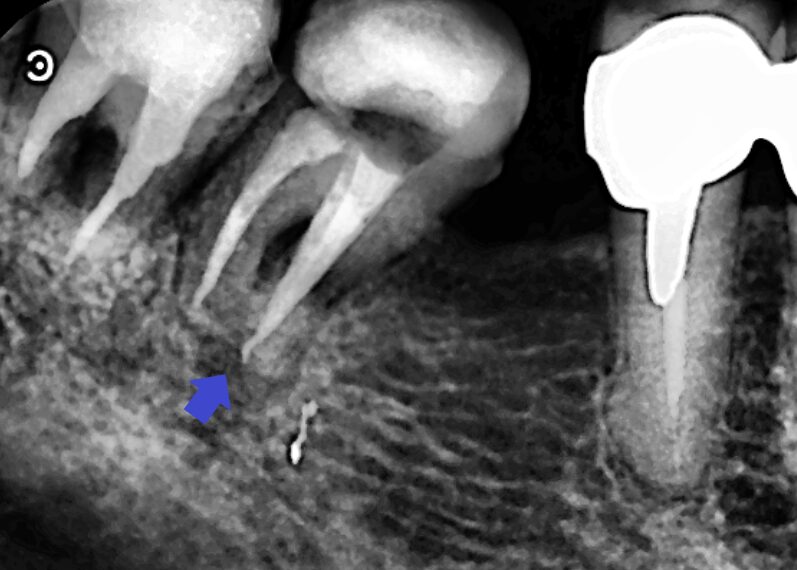

下顎第一大臼歯の近心根の冠状断のCT画像です。

矢印の下顎第一大臼歯の近心根の先に膿の影がみられます。近心根の根管は一本だけでした。